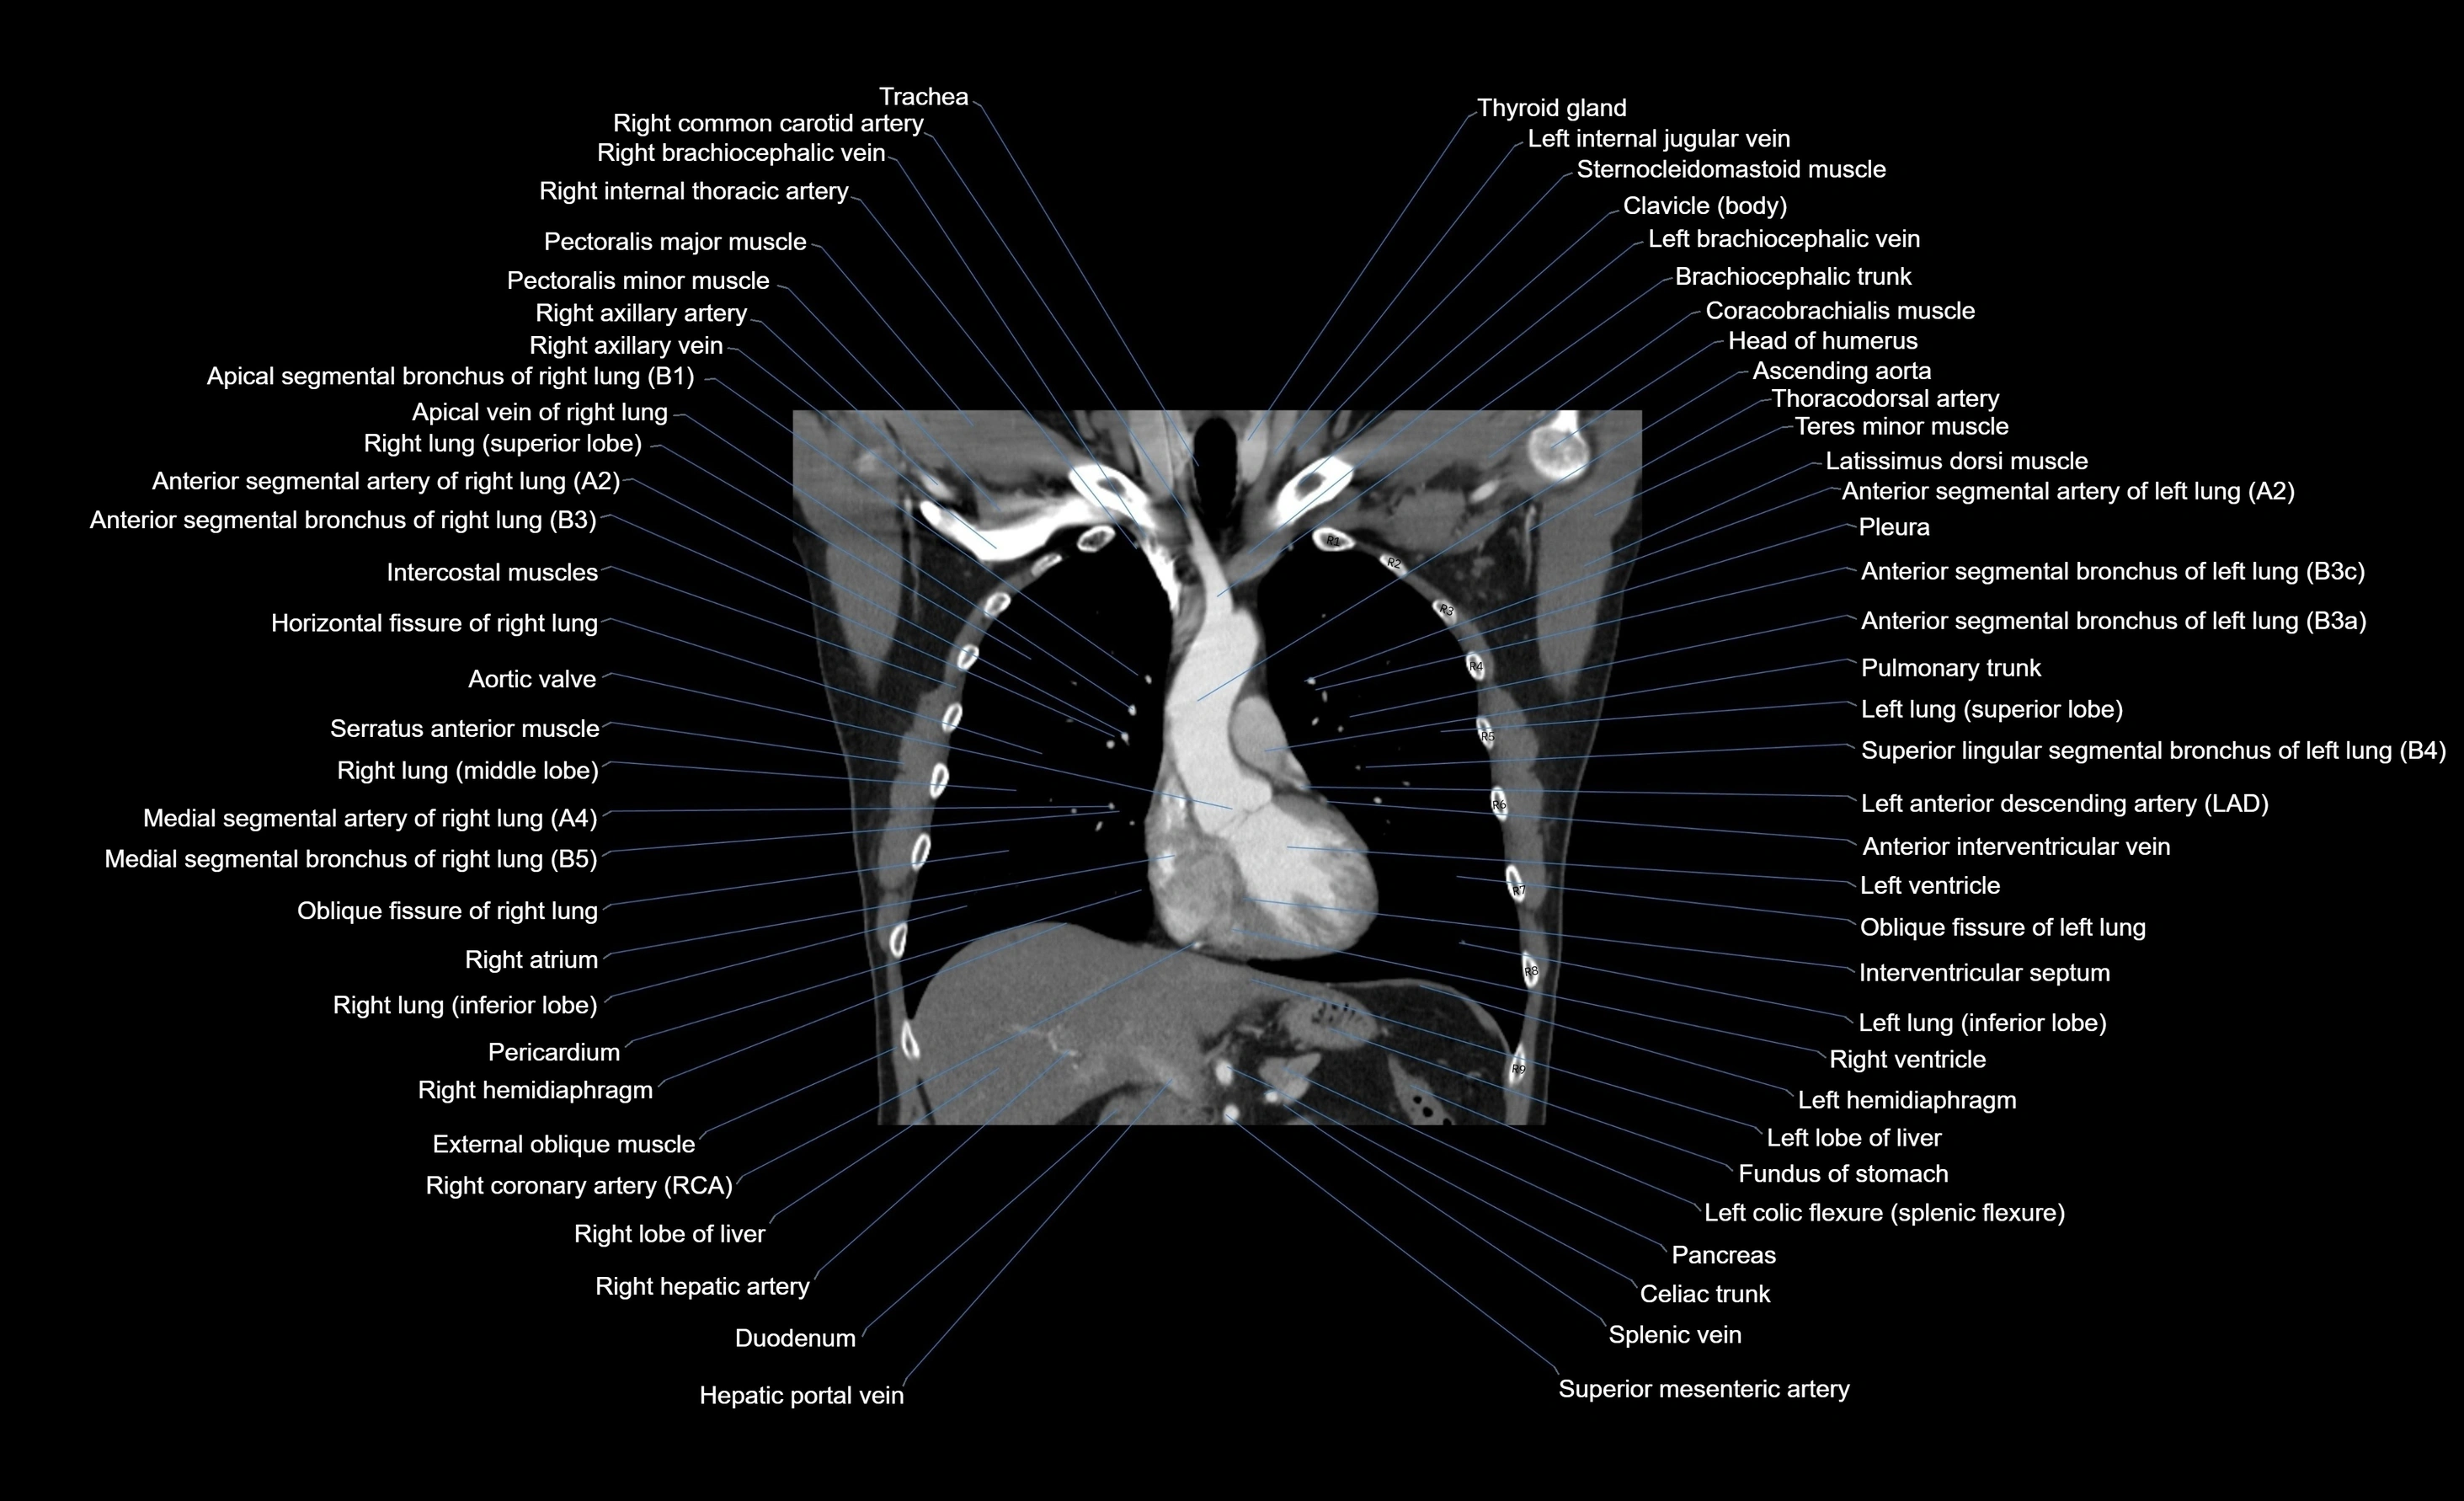

CT images